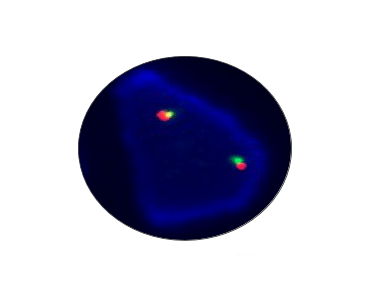

NTRK1 Breakapart

Probe Description: NTRK1

Cat.No.: CF1015